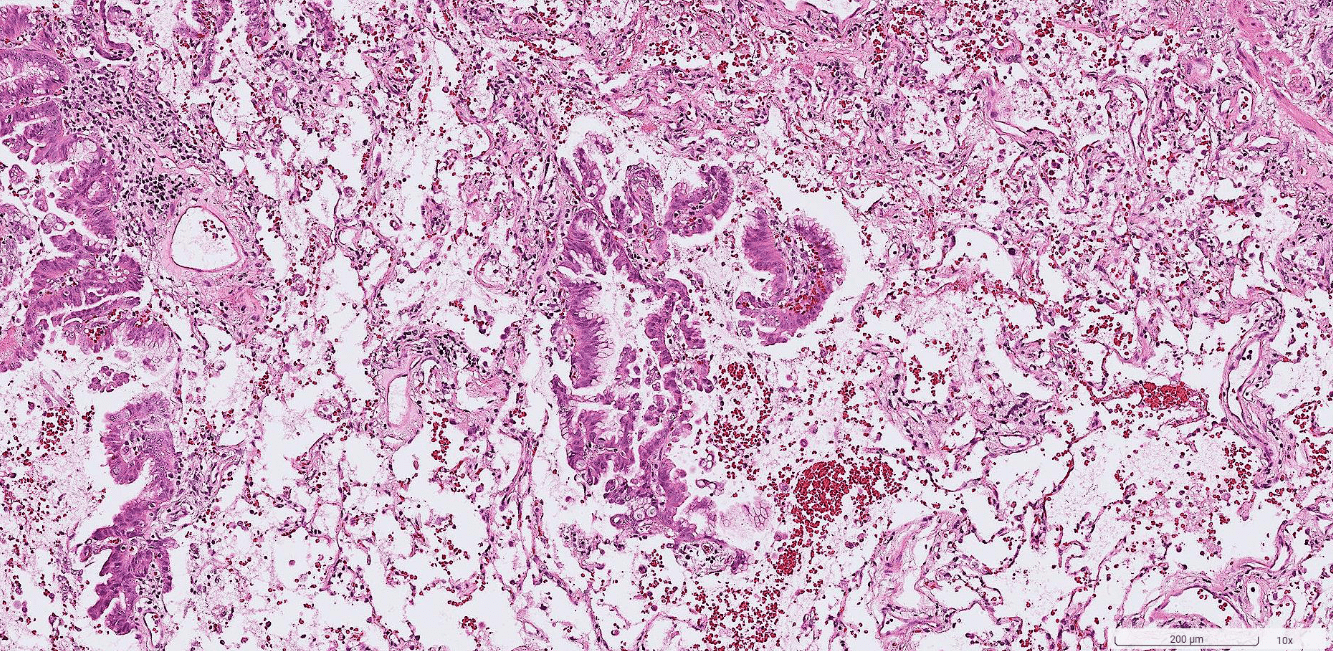

colon cancer